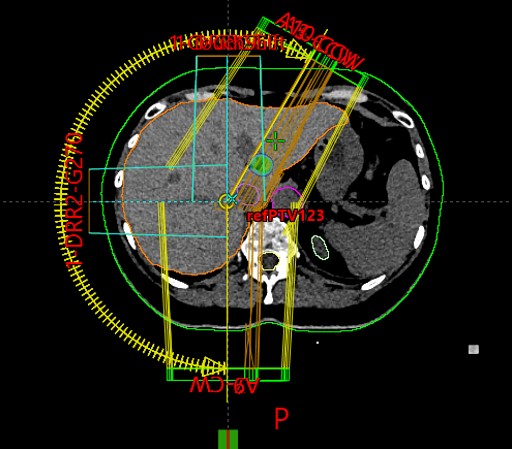

SABR meta hepatis et pelvis (21.11.2017.)

Rezultat – 47 mjeseci nakon RK

potpuni nestanak tretiranih lezija